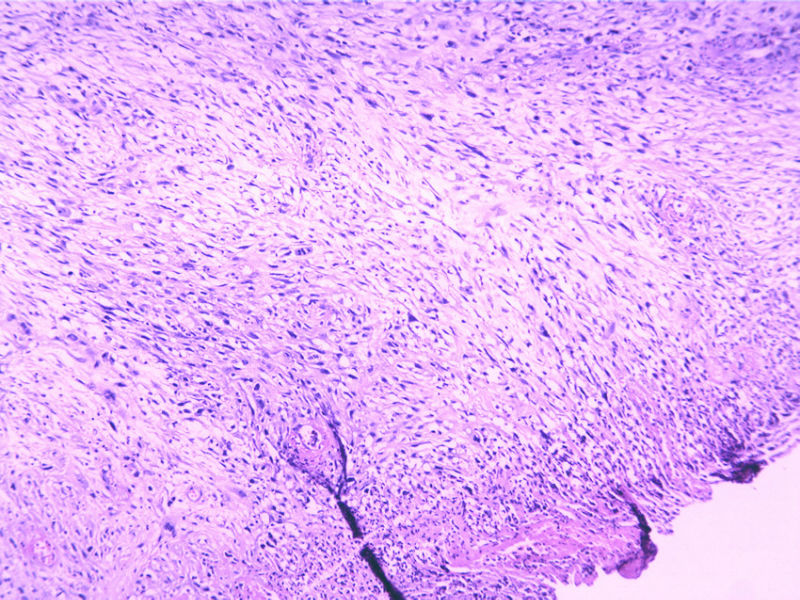

瞧这个小腿肿物,再看IHC(48Y,V2X1X1cm)

• 瞧这个小腿肿物,再看IHC(48Y,V2X1X1cm)图2

图2

梭形细胞肿瘤。倾向为低度恶性神经源性肿瘤,平滑肌、纤维肌纤维母细胞、组织细胞来源肿瘤鉴别。

有包膜吗?细胞有异性,考虑恶性

病史太简单啦,生长时间?是否有包膜?神经鞘瘤的细胞异形完全可以这样的。

低度恶性肿瘤,首先考虑MPNST,其次为纤维母细胞性肿瘤,需要做标记。